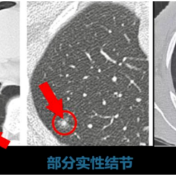

肺结节≠肺癌,早期肺结节可手术治愈,肺结节是影像学显示直径≤3cm的类圆形阴影。常见类型有如下三种:磨玻璃结节→像云雾状的淡淡阴影;实性结节→密度均匀的白色团块;混合型结节→部分实性部分磨玻璃。